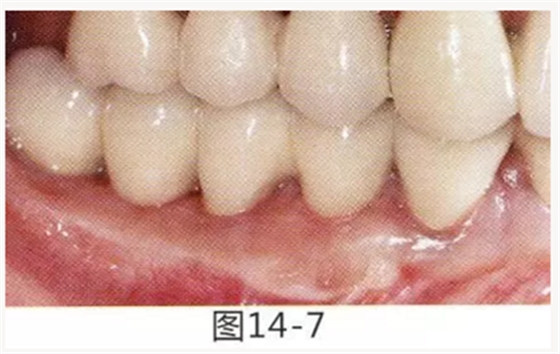

圖14-7 配戴最終修復體完成5年后的狀態(tài)。保持良好。